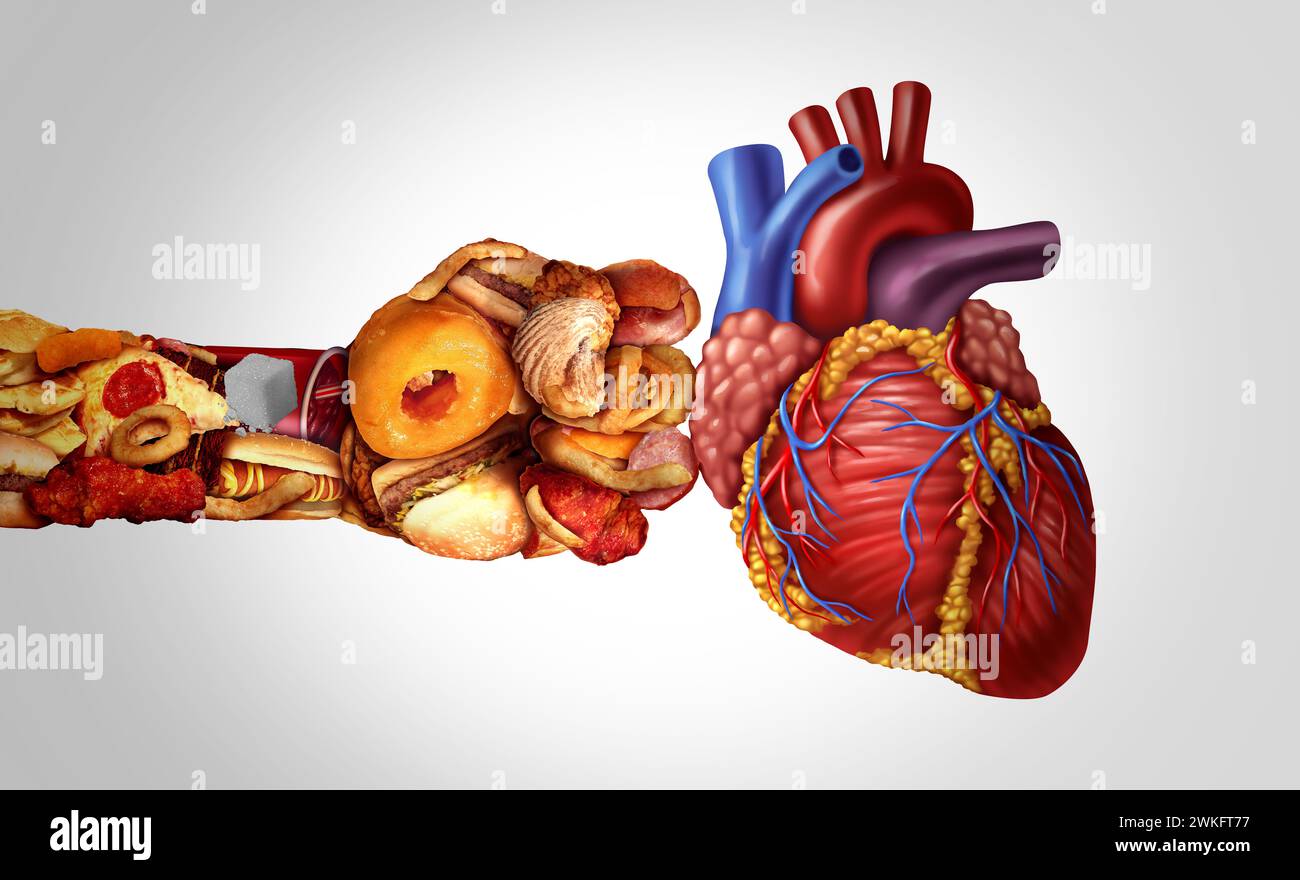

Unhealthy Eating Heart attack as junk food or and high cholesterol fastfood hitting hard the human cardiovascular organ disease as atherosclerosis Stock Photohttps://www.alamy.com/image-license-details/?v=1https://www.alamy.com/unhealthy-eating-heart-attack-as-junk-food-or-and-high-cholesterol-fastfood-hitting-hard-the-human-cardiovascular-organ-disease-as-atherosclerosis-image597179275.html

Unhealthy Eating Heart attack as junk food or and high cholesterol fastfood hitting hard the human cardiovascular organ disease as atherosclerosis Stock Photohttps://www.alamy.com/image-license-details/?v=1https://www.alamy.com/unhealthy-eating-heart-attack-as-junk-food-or-and-high-cholesterol-fastfood-hitting-hard-the-human-cardiovascular-organ-disease-as-atherosclerosis-image597179275.htmlRF2WKFT77–Unhealthy Eating Heart attack as junk food or and high cholesterol fastfood hitting hard the human cardiovascular organ disease as atherosclerosis